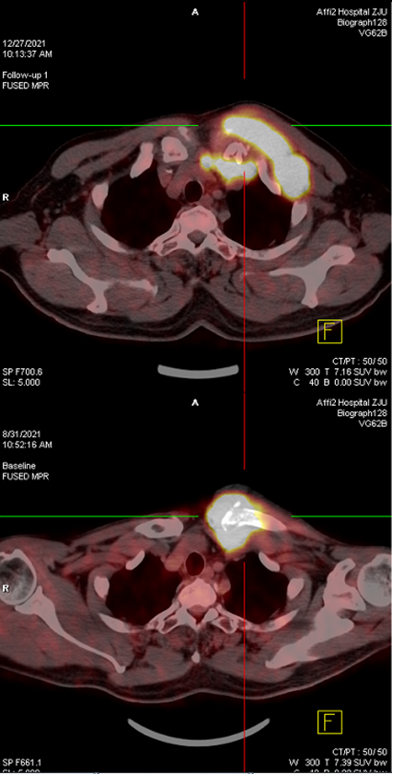

➤2021-12-27查PET-CT示:左锁骨胸骨端病理性骨折伴周围软组织肿块,左颈部、左锁骨区、胸骨后、胸骨左缘多发肿大淋巴结,糖代谢异常增高,较前病灶增多,考虑疾病进展。

化疗后复查(上:2021-12-27,下:2021-8-31)